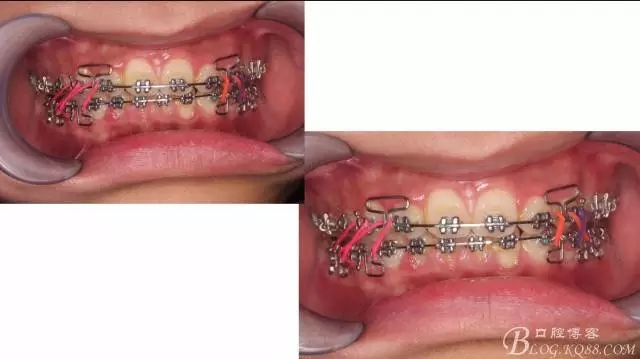

下頜配合多曲方絲,三角牽引,調(diào)整咬合。

中線不齊,咋辦?繼續(xù)哄哄患者配合,2牽+斜牽。

努力沒有白費,中線基本對齊!